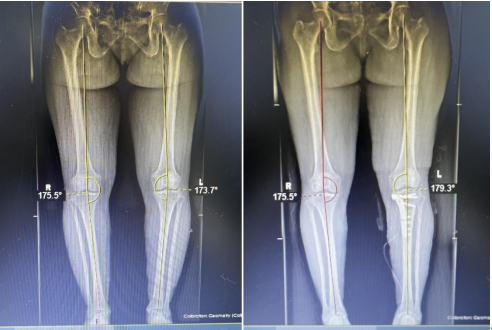

近日,黔江中心医院骨关节科团队率先在重庆地区完成APTT-HTO(胫骨结节中腘肌前—胫骨高位截骨)矫形保膝手术。患者代某某,女,56岁,因“右膝关节反复疼痛4年余,加重伴畸形2年余”家属陪同就诊骨关节科。骨关节科团队在详细评估患者病情后,决定为其实施APTT-HTO(胫骨结节中腘肌前-胫骨高位截骨)矫形保膝手术。手术由骨关节科吴相阳主任医师主刀,在麻醉科、手术室等多科室的紧密配合下,顺利完成。手术切口小(约4—5cm)、手术时间短,手术创伤小,出血量极少。术后患者左下肢力线矫正情况良好,术后第二天便能在医护人员的协助下借助辅助器具下床活动。经过进一步的康复治疗,患者有望在短时间内恢复正常生活。

骨关节科团队率先在重庆地区完成APTT-HTO(胫骨结节中腘肌前—胫骨高位截骨)矫形保膝手术,标志着我院骨关节科在关节外科领域取得重大突破,为膝关节骨性关节炎患者带来了更高效、创伤更小的手术治疗选择。它通过在胫骨高位进行截骨,矫正下肢力线,将膝关节负荷从磨损严重的内侧间室转移至相对正常的外侧间室,从而缓解疼痛,改善关节功能,延缓关节退变,促进关节软骨再生,为膝关节骨性关节炎患者提供了一种新的治疗选择,特别是对渝东南片区人民群众是更好的治疗方法,让他们迅速摆脱膝关节骨性关节炎疼痛和功能障碍的痛苦折磨,更好地恢复健康,回归社会生活。同时,这也将进一步推动我院骨关节科的发展,提升医院的整体医疗水平。